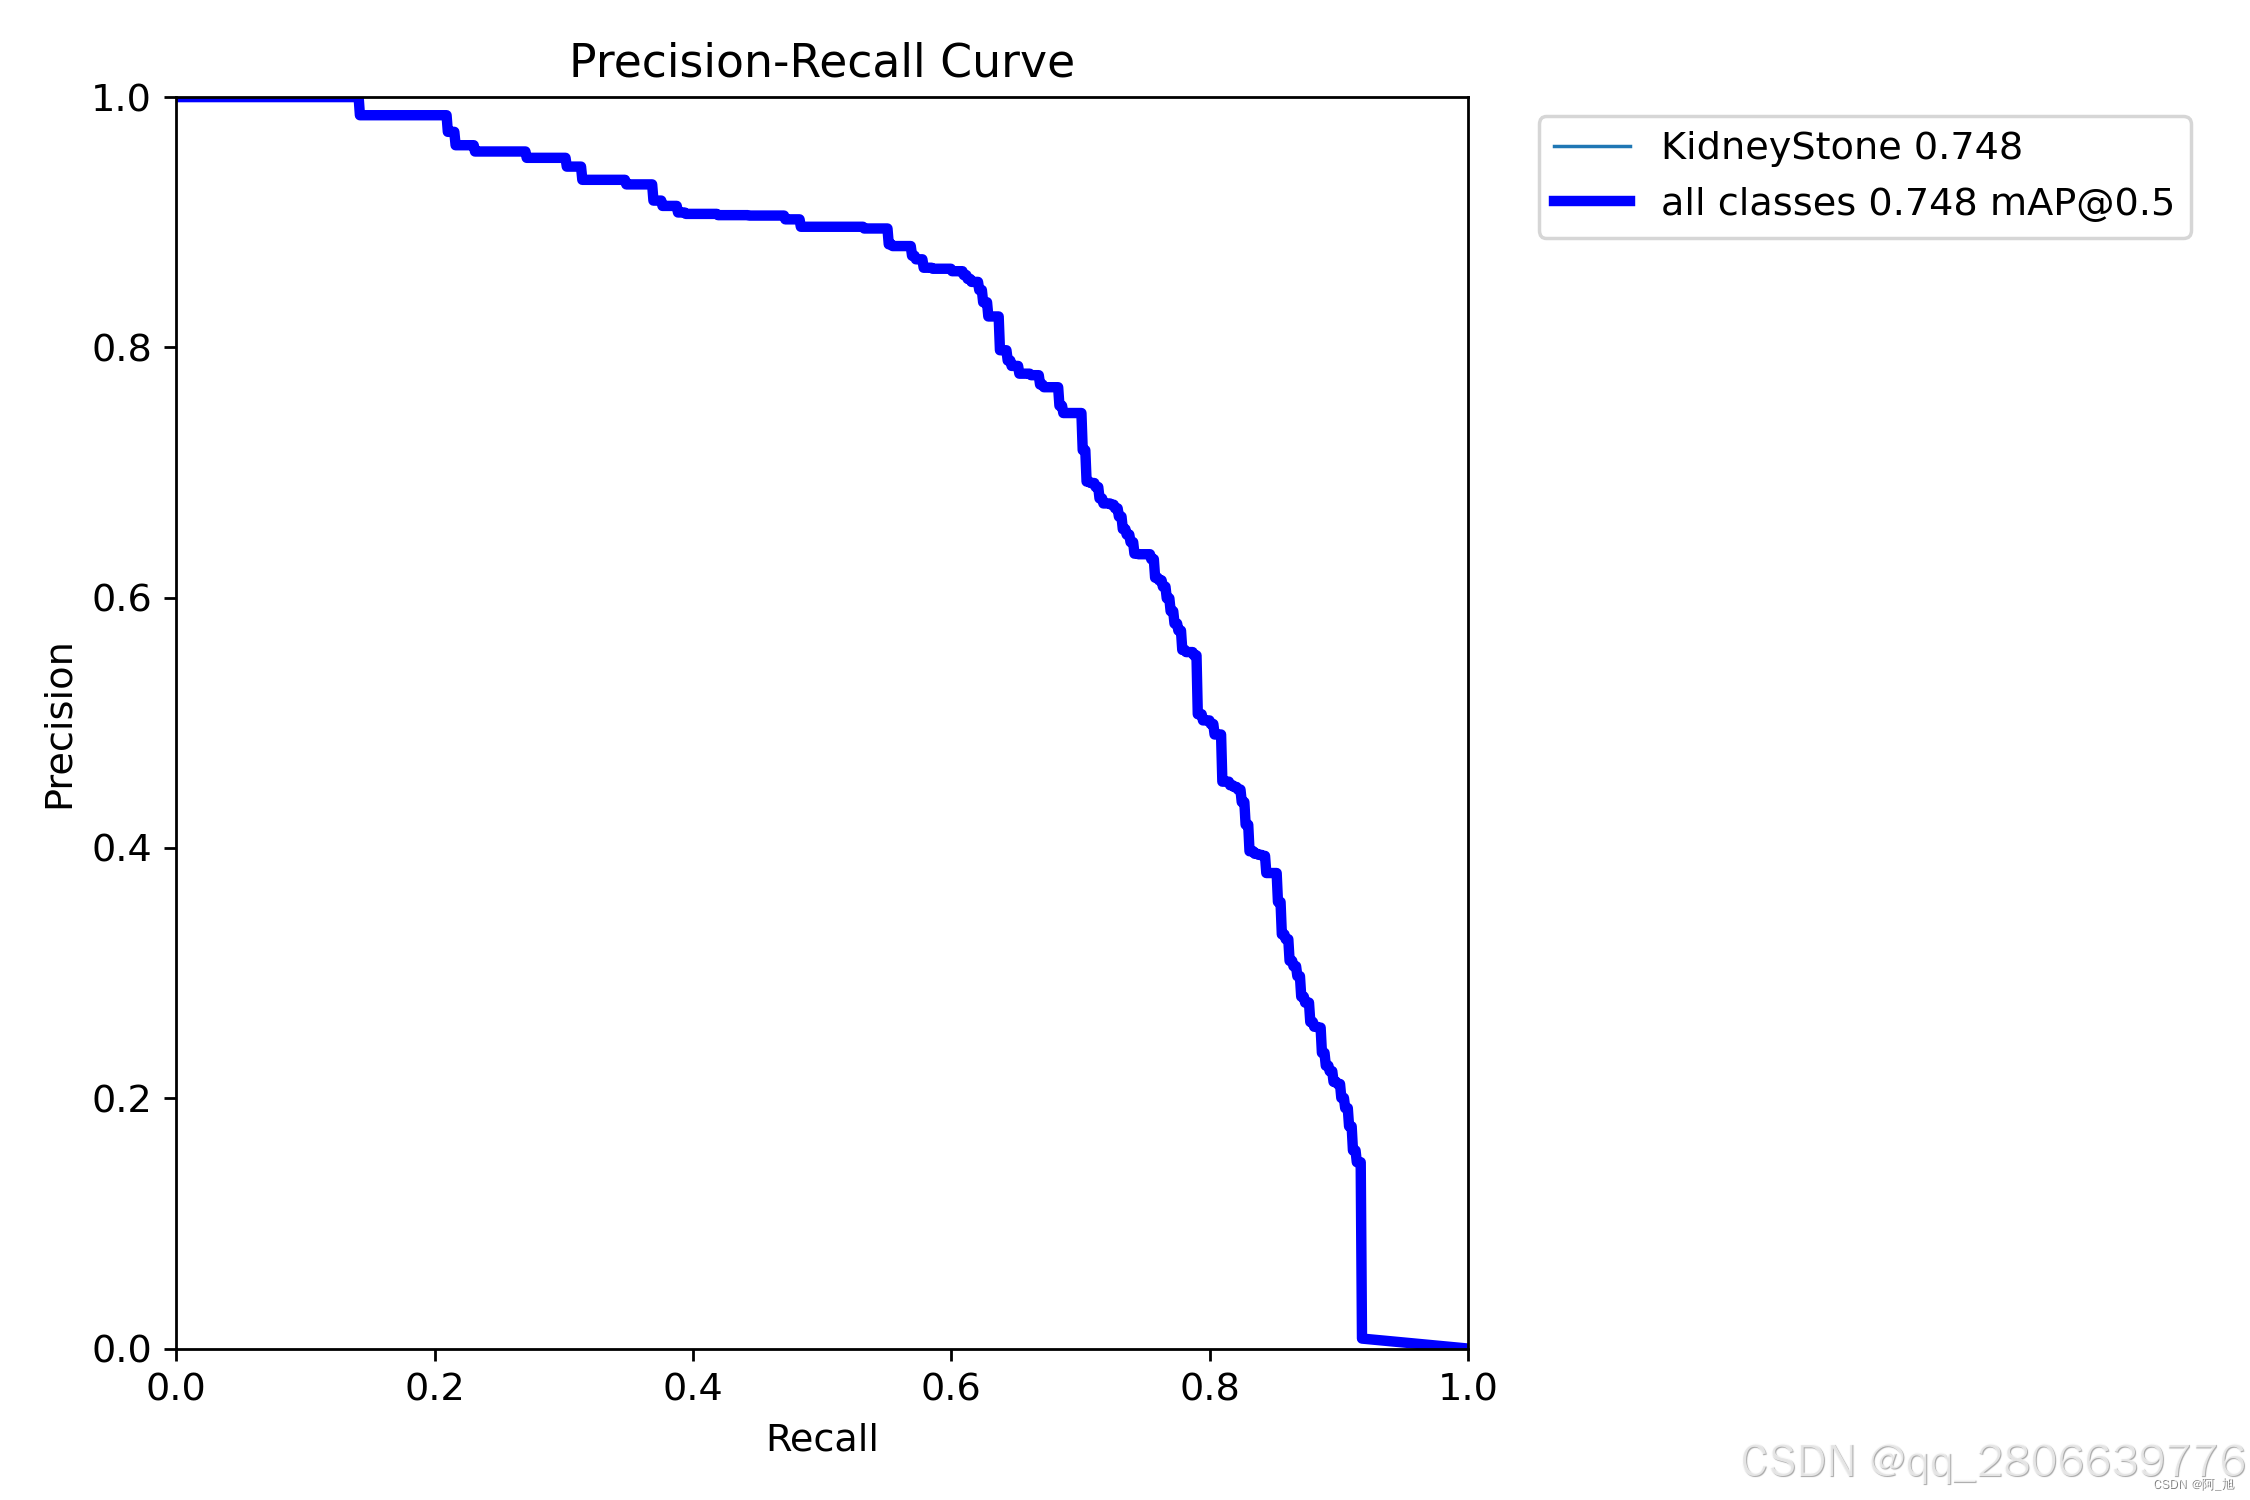

CT扫描图像的肾结石智能检测系统在医疗诊断方面提供了一种快速、准确的辅助工具,显著提高了医生识别和评估肾结石的效率。本文基于YOLOv10深度学习框架,通过1300张CT扫描的肾结石相关图片,训练了一个进行肾结石目标检测的模型,可以对CT扫描图像中的肾结石进行实时检测。并基于此模型开发了一款带UI界面的肾结石智能检测系统,更便于进行功能的展示。该系统是基于python与PyQT5开发的,支持图片、视频以及摄像头进行目标检测,并保存检测结果。本文提供了完整的Python代码和使用教程,给感兴趣的小伙伴参考学习,完整的代码资源文件获取方式见文末。